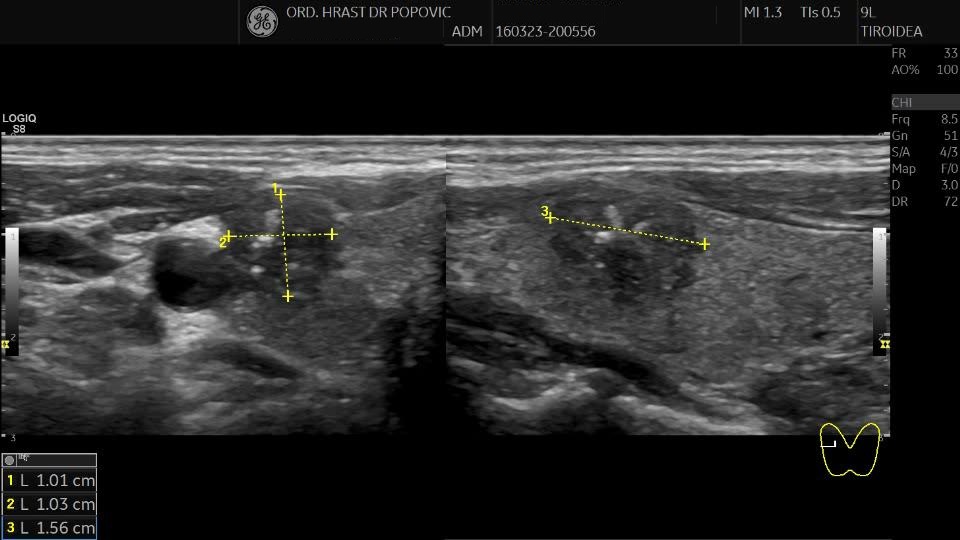

Ultrazvučni pregled štitaste žlezde - Papilarni karcinom štitaste žlezde - ACR TI-RADS 5

Ultrasound examination of the thyroid gland - Papillary carcinoma of the thyroid gland ACR TI-RADS 5